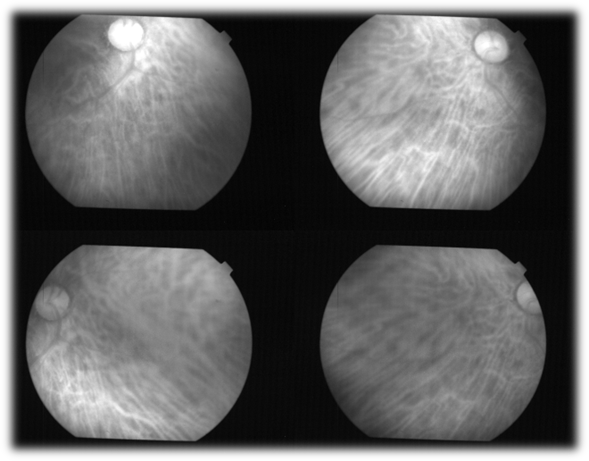

Figure 6. The image shows the optic nerve and retina of the left eye. Retinal blood vessels are sparse, and they all exit and enter through the optic nerve. This vasculature handles only 2% of the blood that leaves the first intracranial branch of the internal carotid artery (Herrera AS, et al., 2025, ©).

Figure 7. The choroid in humans is only visualized in the living patient, using wavelengths greater than 750 nanometers, which allows us to observe the large number of fenestrated capillaries that make it up, as well as in the choroidal plexus of the ventricles of the brain. In humans, the choroid handles 98% of the blood that enters the eyeball (Herrera AS, et al., 2025, ©).